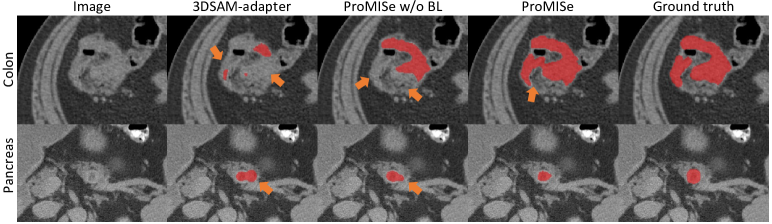

Fig. 4: Qualitative results. BL denotes boundary-aware loss. The major differences are highlighted by orange arrows.

Qualitative results. Fig. 4 shows qualitative visualizations from top-performing promptable methods. ProMISe yields results that closely align with the ground truth. 3DSAM-adapter [8] fails to detect certain regions that ProMISe captures, even without the boundary-aware loss. This indicates the improved generalizability of the model through our proposed modifications. Moreover, the use of the boundary-aware loss yields robust segmentations, alleviating issues of both under-segmentation for colon and over-segmentation for pancreas tumors, respectively. Notably, the boundary-aware loss improves segmentation not just for the irregularly shaped colon tumors but also for the pancreas tumors, which typically have a more regular, rounded shape. However, slight under-segmented areas are found in pancreas segmentation.